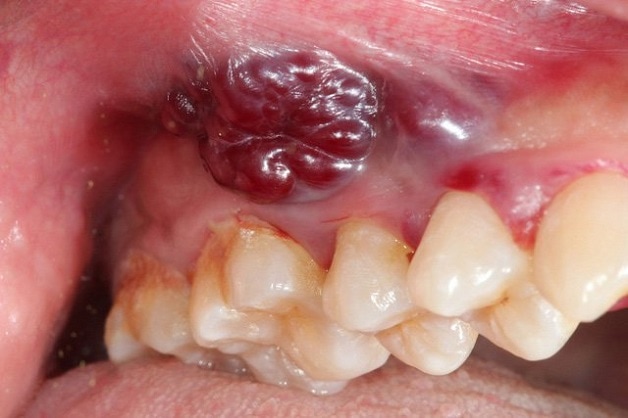

4. Có mủ chảy ra từ vết thương

Đây là dấu hiệu chắc chắn nhất của nhiễm trùng. Bạn có thể thấy một dịch lỏng màu trắng, vàng hoặc xanh chảy ra từ huyệt ổ răng, đặc biệt là khi ấn nhẹ vào vùng nướu xung quanh. Mủ thường có mùi hôi rất khó chịu.